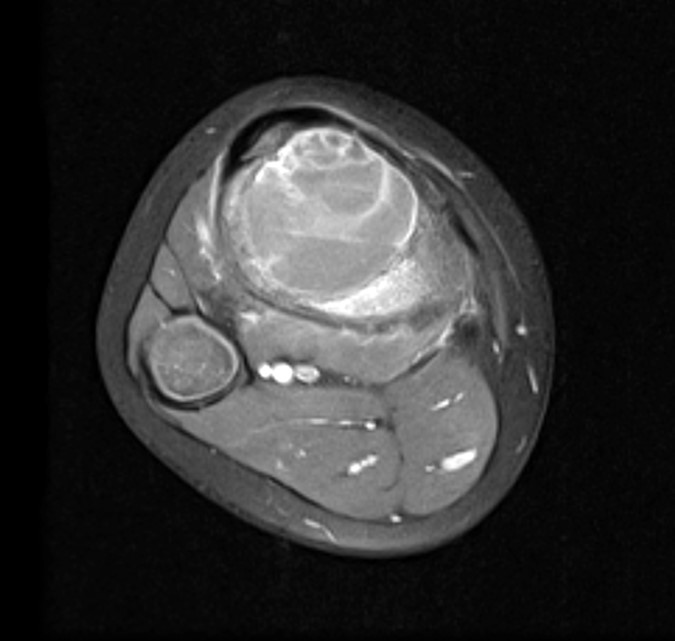

- Xray:

- CT scan:

- Well delineated lytic lesion, usually with thin rim of reactive bone

- Fluid-fluid levels occasionally visible

- MRI:

- Multiloculated cyst with characteristic fluid-fluid levels

Radiology images